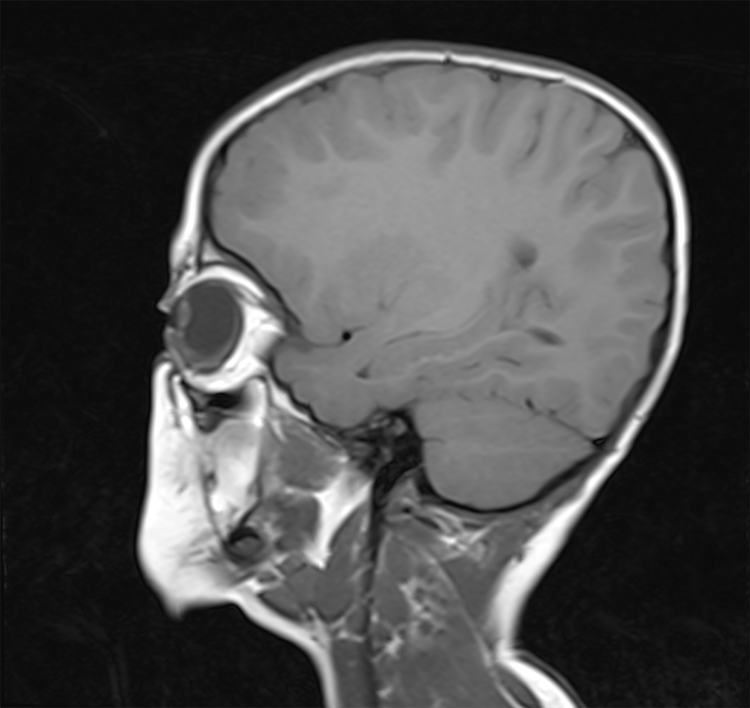

#AJNRcc >> November 11, 2024 >> What is the diagnosis for this 54-year-old woman admitted for paresthesia of the lower limbs with laboratory tests revealing an HIV infection? Submit your answer at https://t.co/6aANs07WZ8.